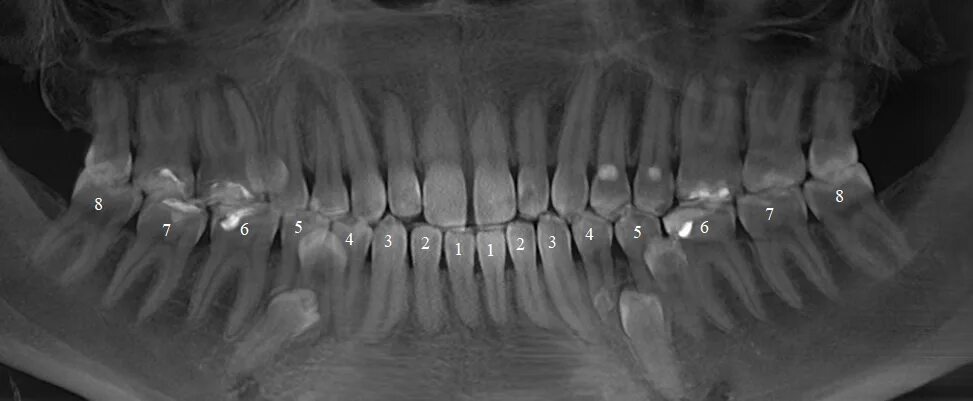

Могут ли быть 9 зубы